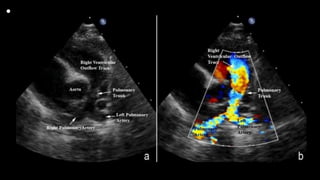

• This still frame image

of a parasternal short

axis view of the

echocardiogram of a

patient with tetralogy

of Fallot demonstrates

the antero-cephalad

deviation of the outlet

septum into the right

ventricular outflow

tract.

• A slightly modified view (a), angled to optimize

imaging of the pulmonary arteries in the patient

imaged to produce Figure 6, reveals significant

hypoplasia of the pulmonary trunk and the

pulmonary arteries, which result from the antero-

cephalad deviation of the outlet septum. The

pulmonary valvar leaflets are not visualized. In panel

b, colour Doppler has been used, and demonstrates

turbulence and acceleration of the flow of blood in

the right ventricular outflow tract, originating at the

level of the deviated outlet septum. The turbulence

continues into the hypoplastic pulmonary trunk and

pulmonary arteries.